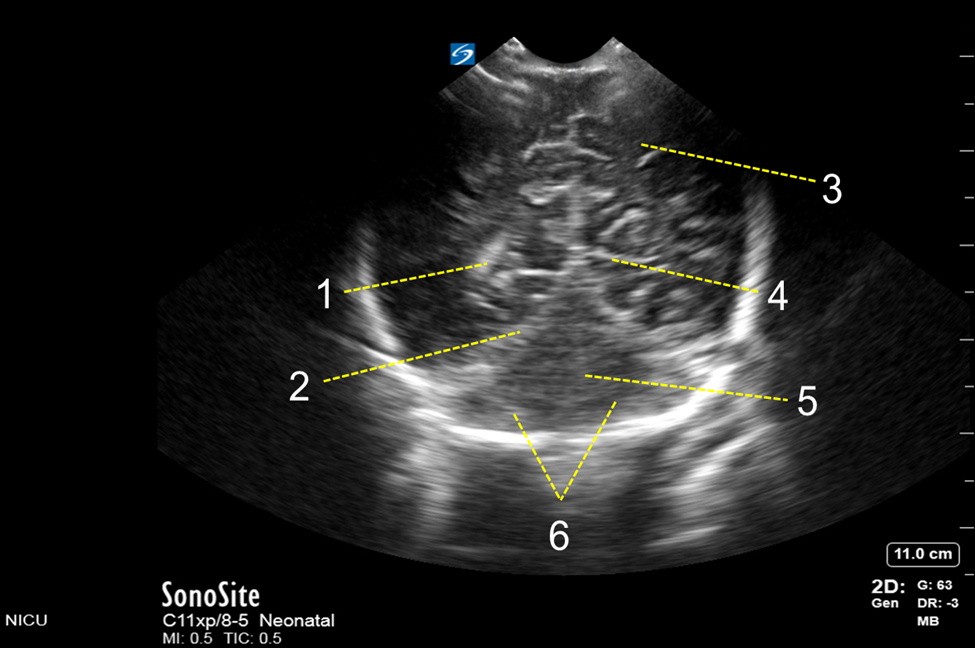

Neonatology Posterior Fontanelle Mid-Coronal View Image

1. Occipital Horn of Lateral Ventricle

2. Tentorial Area

3. Occipital Lobe

4. Calcarine Fissure

5. Cerebellar Vermis

6. Cerebellar Hemisphere